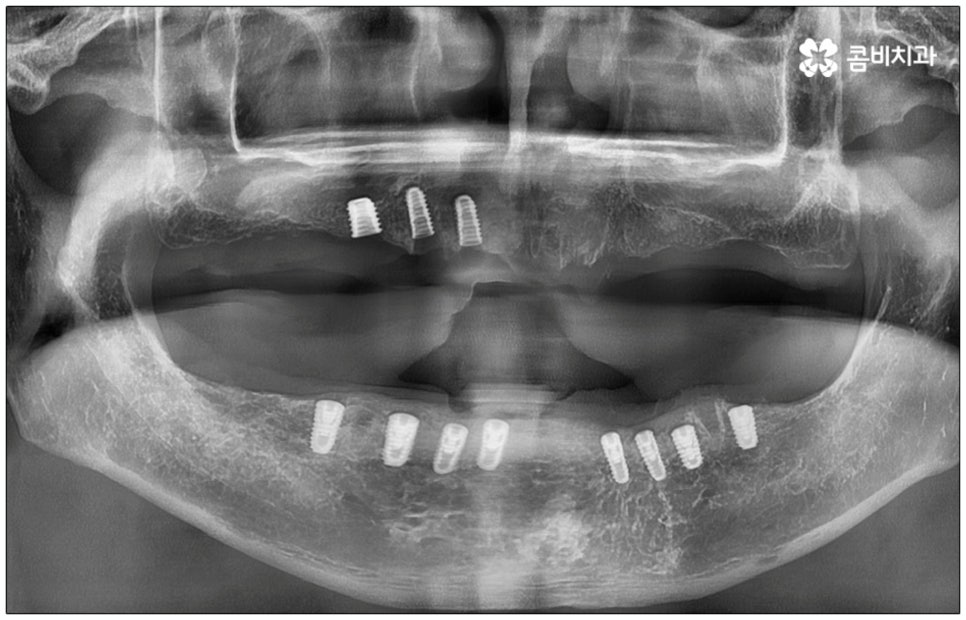

전신 질환을 앓고 있는 분들이나 고령의 환자분들, 다수의 임플란트가 필요한 분들의 경우 컴퓨터 분석을 활용한 임플란트 방식을 통해 도움받아 볼 수 있는데요. 네비게이션 임플란트라고 불리는 이 방식은 첨단 장비를 통해 육안으로 확인하기 어려운 구강 내부의 골조직, 신경 등의 해부학적 구조를 살펴본 다음 3D 모의 수술을 통해 최적의 수술 경로를 찾아내어 가이드를 제작하고 이를 장착하여 그대로 진행하기 때문에 보다 정확하고 안전하게 노인임플란트 수술을 진행할 수 있습니다.

이러한 네비게이션 임플란트 방식은 디지털 기술로 위험 요소를 사전 분석하여 식립 위치와 각도를 보다 정교하게 예측하기 때문에 임플란트 부작용의 발생률을 낮추고 식립 안정성을 높일 수 있는데요. 무절개 또는 최소절개 수술이기 때문에 시술 시간이 짧고 통증이 적으며 회복 기간이 빠르다는 장점을 가지고 있으나 정밀 검진 후 상황상 골유착 과정의 안정성이 떨어질 수 있는 케이스의 경우에는 절개 및 개방 후 수술을 진행하는 것이 좀 더 유리하기 때문에 꼼꼼한 검진, 정확한 판단, 의료진의 높은 숙련도가 굉장히 중요하다고 할 수 있어요.

특히 다수의 치아를 상실했을 때 전체적인 교합, 골조직 및 잇몸 상태, 얼굴형과의 조화 등 모든 부분을 종합적으로 고려하여야 하며 노인임플란트 수술의 경우 다양한 변수가 발생할 수 있기 때문에 이러한 고난도 임플란트 케이스에 노련하게 대처할 수 있도록 풍부한 임상 경험과 노하우를 갖춘 의료진인지, 정밀 검진 기계를 보유하고 있는지, 처음부터 끝까지 철저한 케어 시스템을 갖추고 사후 관리까지 꼼꼼하게 진행하는지 등을 잘 살펴보시고 임플란트 수술을 진행할 치과를 신중하게 선택하시길 권유드리고 있습니다.

특히 만 65세이상 부분 무치악 환자의 경우에는 노인임플란트 수술을 받을 때 건강 보험 혜택을 통해 평생 2개까지 자기 부담금 30%로 보다 저렴하게 이용해 볼 수 있으니 이에 대해서도 잘 알아보시고 도움받아 보시길 바라고 있어요. 만약 구강 질환이 너무 많이 진행되어 잇몸뼈가 이미 상당 부분 녹아서 뼈이식이 추가로 이루어져야 하거나 상악동 거상술과 같이 노인임플란트 수술의 안전성과 지속성을 높이기 위한 사전 처치가 필요한 경우 등에 있어서는 보험 혜택 대상에서 제외되는 부분이 있을 수 있으니 자세한 사항들은 의료진과 꼼꼼하게 상담해 보시고 진행해 보시면 좋을 거예요.